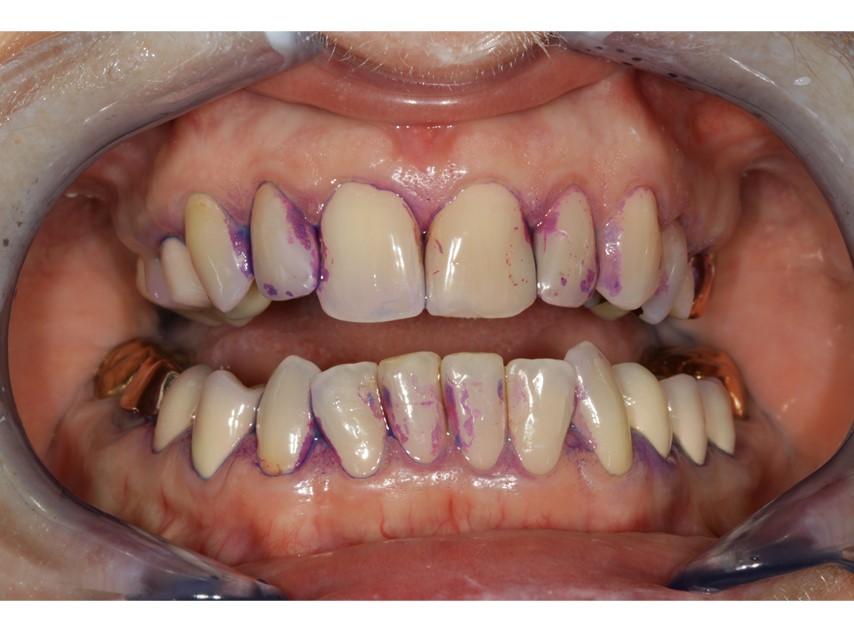

Es ist von Vorteil, bereits beim Einsetzen der Suprakonstruktion die TST/BAS (6-Punkt-Messung) aufzunehmen. Der Wert dient als Baseline und sollte in der Patientenkartei festgehalten werden. Einmal jährlich empfiehlt es sich, TST/BAS an Implantaten aufzunehmen, um einen möglichen Abbau des periimplantären Stützgewebes zu ermitteln (Abb. 2). Dieser sollte mit der Baseline verglichen werden. Stellt sich eine Abweichung des Referenzwertes dar, ist es ein erster Hinweis auf einen entzündlichen Prozess. Periimplantitis kann mit weiterer Diagnostik (Röntgenbilder) im Frühstadium erkannt und behandelt werden. Laut der aktuellen Klassifikation von periimplantären Erkrankungen kann in Abwesenheit vorheriger Untersuchungsdaten die Diagnose einer Periimplantitis aufgrund der Kombination von Vorhandensein von Blutung und/oder Suppuration bei schonungsvollem Sondieren und Sondierungswerten von ≥6 mm gestellt werden (Abb. 3). Bei der Aufnahme der Sondiertiefen kann eine Kunststoffsonde durch Flexibilitätseigenschaften im Vergleich zu einer starren Stahlsonde einen Vorteil bieten (Abb. 4). Das gilt insbesondere bei Implantaten, die sich durch volumenöse Aufbauten als schwer zugänglich erweisen. Eine weitere Schwierigkeit beim Sondieren kann das Platform-Switching (Rö-Bild, Abb. 5) sein (Versorgung von Implantaten mit Durchmesser-reduziertem Aufbau). Die Sonde kann beim Messvorgang auf die Implantatschulter stoßen.

Periimplantäre Mukositis ist gekennzeichnet durch Bluten auf Sondieren (BAS) und sichtbaren Entzündungszeichen (10).

Gibt es erste Anzeichen einer Blutung auf Sondieren, müssen diese engmaschig kontrolliert werden. Daher sollten regelmäßige Nachkontrollen (z. B. alle drei Monate) zur Prävention und zur frühzeitigen Diagnostik einer Periimplantitis geplant werden.